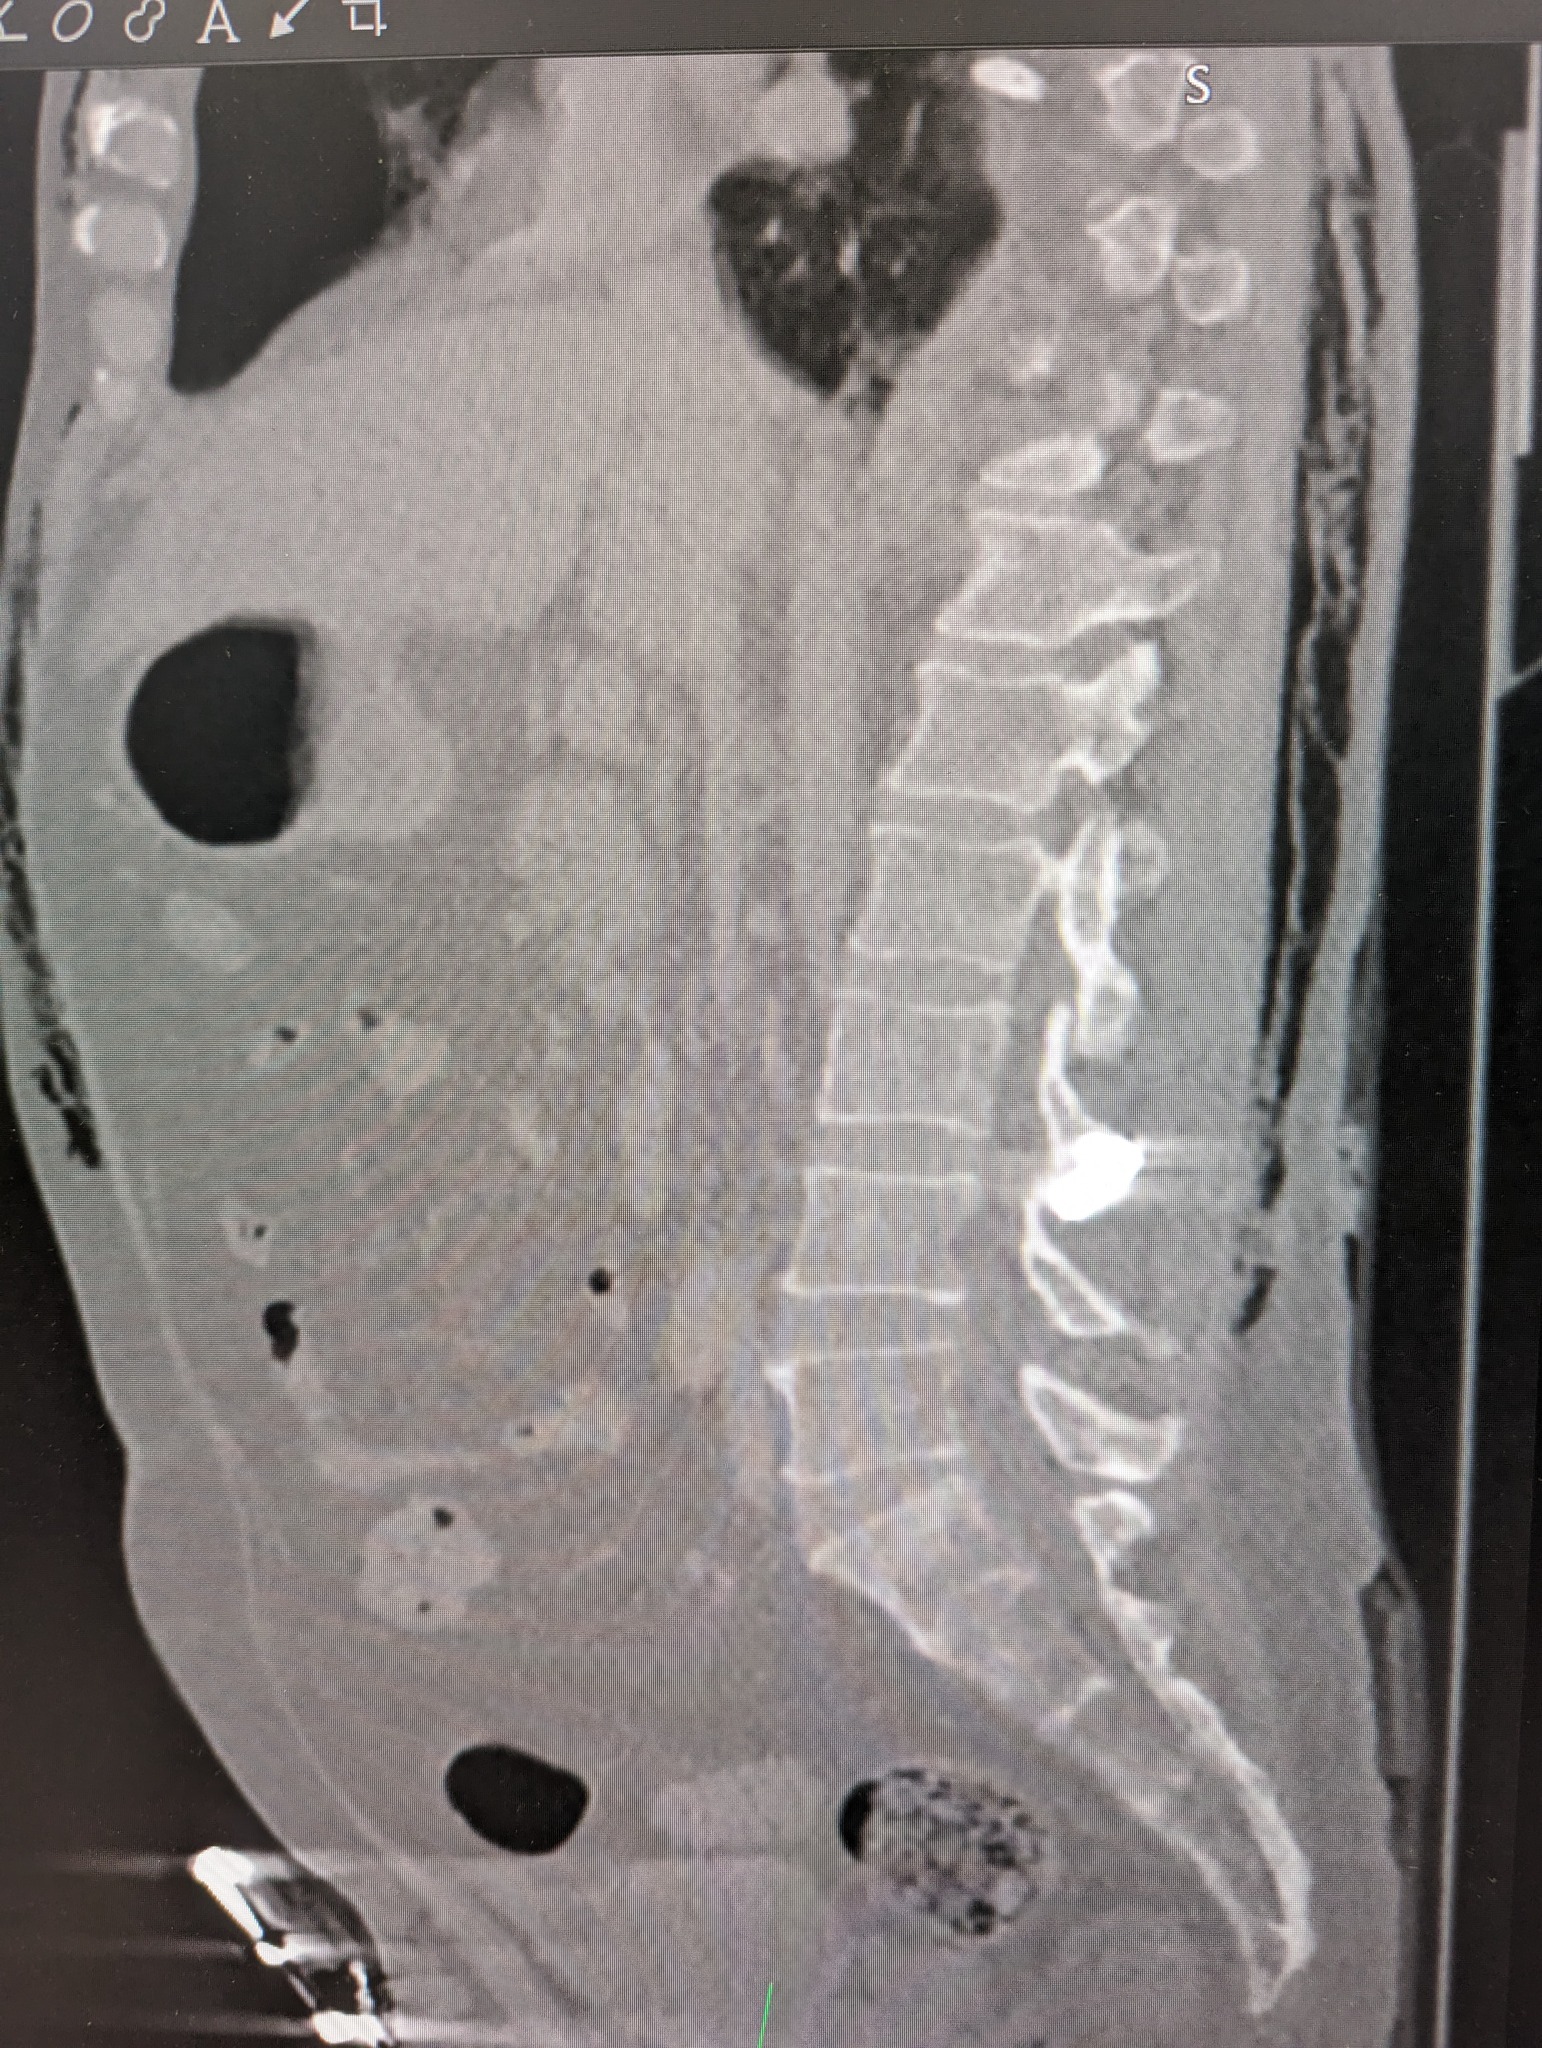

После вчерашнего обстрела Киева обломок ракеты попал жителю столицы прямо в позвоночник и застрял там. В самой известной столичной больнице провели необычную операцию по спасению человека от обломка металла, который застрял между позвонками.

Один из раненных вчера мужчин остался с обломком ракеты в спине - металл застрял в фасеточном суставе между позвонками L3 и L4.

Благодаря компьютерной томографии (КТ) и электронно-оптическому преобразователю обломок был четко локализован. Это дало возможность провести точечную операцию по удалению куска металла.